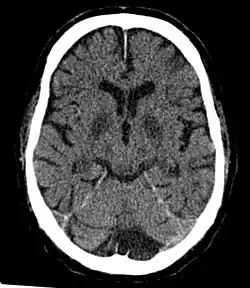

CT in a person after generalized hypoxia.